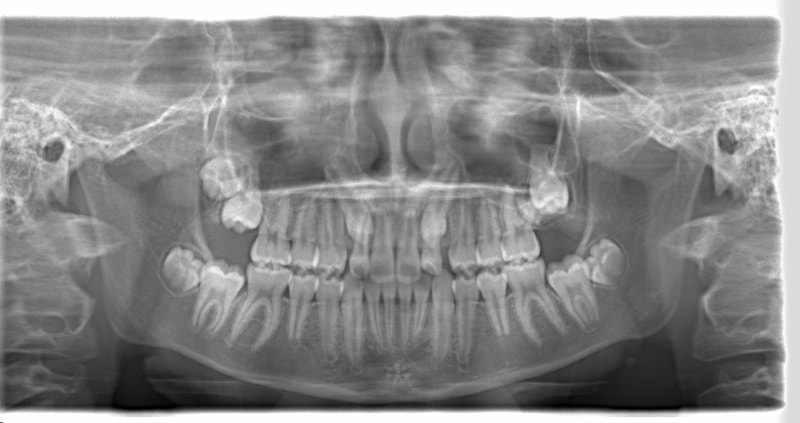

治療法:上顎急速拡大装置+クリアスナップ+フェイスマスク+上顎3番は開窓牽引CT写真にて位置確認

FX(フェイシャルアキシス)は85度なので東洋人の平均値に近く、下顎が前方に過剰成長するリスクは強くはありません。

しかしやはり上顎は劣成長で、下顎が優位な状態ではあります。

骨年齢は実年齢よりも低めなので、今後下顎の旺盛な成長が見込まれます。

検査時のレントゲン分析では、上下顎の関係は、上顎の劣成長があり下顎前突傾向という値がでておりましたが、前歯ジャンプ後はフェイスマスクの効果もあり、上下顎の関係は正常化しています。

上顎が若干優位になっていますので、今後の下顎の成長のための貯金になっているくらいです。